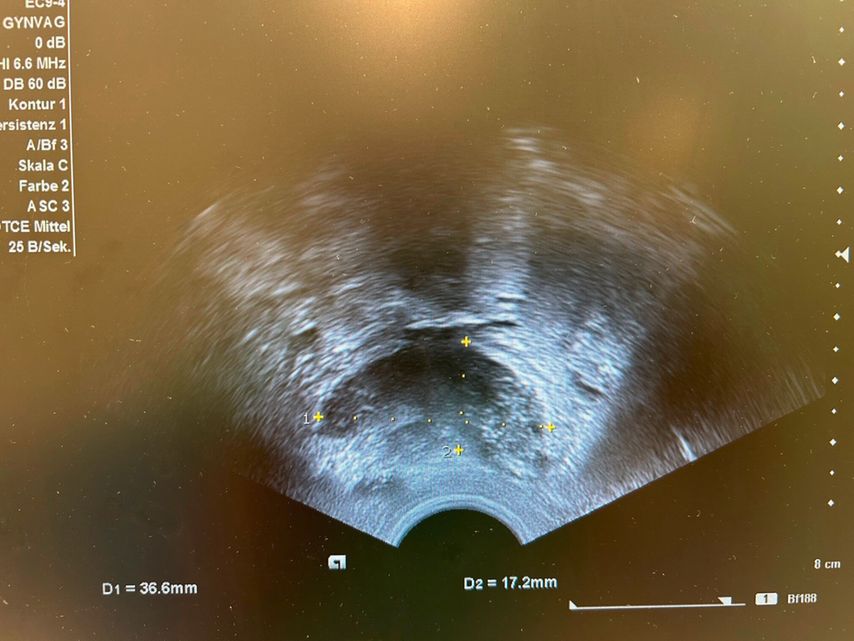

Eine TIE bedeutet eine Gewebeinfiltration von ≥5mm. Die häufigste Lokalisation ist das Ligamentum sacrouterinum. Genauso wie bei Lokalisation in der Vagina oder dem Parakolpium können die damit assoziierten Symptome Dyspareunie, also Schmerzen beim Geschlechtsverkehr, sein. „Diese Endometrioseherde können bei Progredienz zu einer extrinsischen Ureterstenose und chronischen Hydronephrose bis hin zum Verlust der Nierenfunktion führen. Aus diesem Grund ist es entscheidend, dass bei allen Endometriosepatient:innen ein Nieren-US durchgeführt wird“, betonte Sevelda. Eine tief infiltrierende Darmendometriose kann zu Symptomen wie Dyschezie, Hämatochezie, chronischen Unterbauchschmerzen und Obstipation führen (Abb. 1). Ein Ileus tritt jedoch selten auf.

Abb. 1: Bild einer tief infiltrierenden Darmendometriose im Transvaginalultraschall